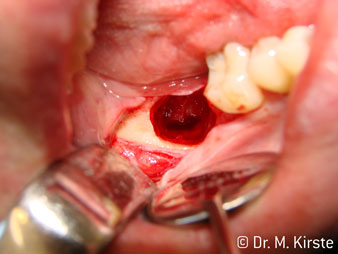

La concezione professionale del sistema di cuscinetti nel cuore della testina del contrangolo assicura un funzionamento silenzioso delle frese; durante l'estrazione di denti e radici (Fig. 4 - 9) si ottiene un taglio estremamente preciso e stabile.